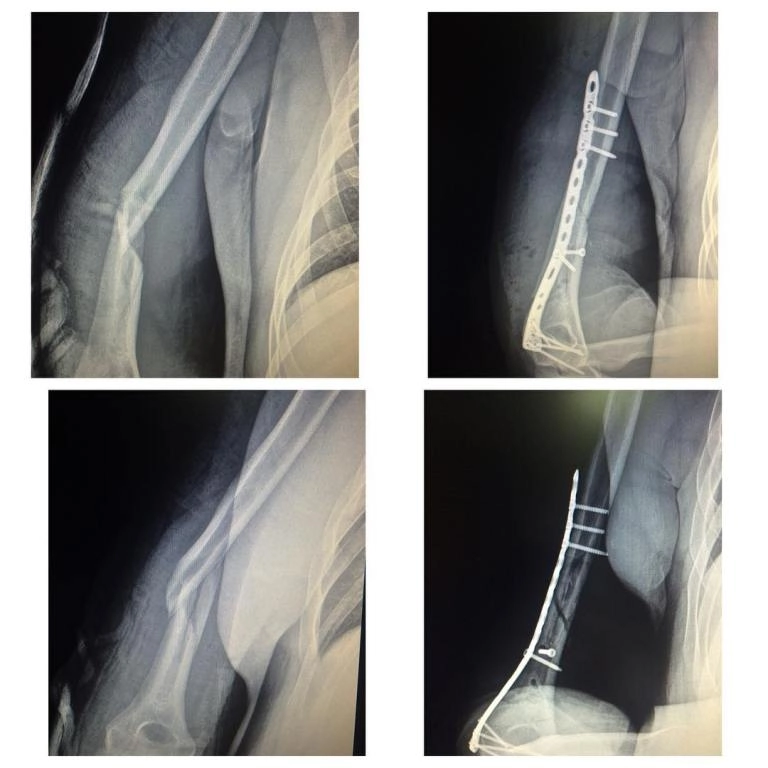

• Также востребованы процедуры по восстановлению связок, остеосинтез костей при переломах разной сложности.